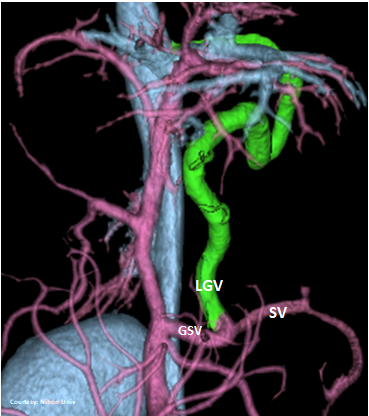

“LGC +RGV +SGV”

Left Gastro-Caval Shunt with Right Gastric Vein and Short Gastric Vein contributions

Courtesy: Nihon Univ